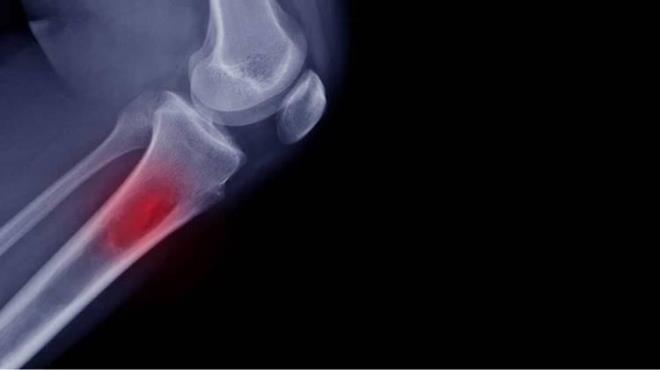

5. OSTEOİD OSTEOMA KEMİK TÜMÖRÜ NEDİR?    Osteoid osteoma kemiğin iyi huylu tümörüdür ve iyi huylu kemik tümörlerinin %10?unu oluşturur. Çocukluk yaş grubunda daha sık görülür. Erkeklerde kadınlara oranla 2-3 kat daha fazla görülür. Genellikle uzun kemikleri tutar (kaval kemiği, uyluk kemiği, kol kemikleri). Diğer kemiklerde de nadir olarak görülmesi mümkündür.

OSTEOİD OSTEOMA KEMİK TÜMÖRÜ NEDİR? Osteoid osteoma kemiğin iyi huylu tümörüdür ve iyi huylu kemik tümörlerinin %10?unu oluşturur. Çocukluk yaş grubunda daha sık görülür. Erkeklerde kadınlara oranla 2-3 kat daha fazla görülür. Genellikle uzun kemikleri tutar (kaval kemiği, uyluk kemiği, kol kemikleri). Diğer kemiklerde de nadir olarak görülmesi mümkündür.